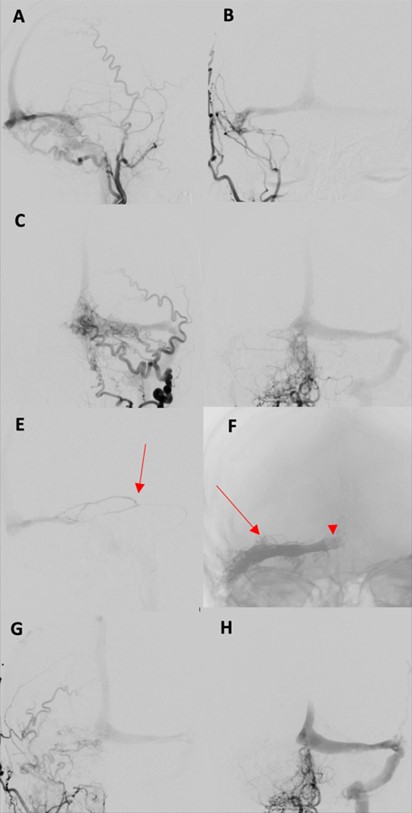

In our retrospective cohort study, the overall initial complete angiographic occlusion was seen in 69.6% (48/69) of patients, with similar (p = 0.47) outcomes between the endovascular (71.4%) and surgical (69.2%) groups. Angioarchitectural complexity (p =< 0.001), fistula location (p = 0.034) and venous drainage patterns (p = 0.027) significantly influenced treatment success in our series. Previous studies have demonstrated that multiple arterial feeders particularly when small, tortuous, or difficult to access, are associated with lower incidence of complete obliteration [25]. Consistent with these findings, lesions with three or fewer arterial feeders in our cohort were associated with higher incidence of complete occlusion compared to those with more than three feeders. Lesions over the convexity or laterally along the transverse or sigmoid sinus often achieve better occlusion, especially when supplied by a single dominant feeder and draining into a single vein or non-functional sinus [25, 26]. In contrast, midline or paramedian fistulas involving the superior sagittal sinus or torcula (Figures 2 & 3) tend to have lower obliteration rates due to complex bilateral arterial supply [25, 26]. These lesions often require bilateral embolization or disconnection to achieve cure, as unilateral approaches are typically inadequate [27]. In our series, location was significantly associated with treatment outcome (p = 0.034), with convexity lesions demonstrating higher initial occlusion rates than other locations. Although higher rates of residual fistula were noted in bilaterally supplied lesions in our series, this difference did not reach statistical significance when compared to unilaterally supplied cases.

AP: Anteroposterior; DSA: Digital Subtraction Angiogram; ECA: External Carotid Artery; MMA: Middle Meningeal Artery; STA: Superficial Temporal Artery.

The management of dAVFs that drain into dural sinuses (Borden type I and II) is fundamentally distinct and requires careful consideration of both the abnormal arteriovenous shunt and the normal venous outflow of the surrounding brain. In such lesions, particularly in the absence of cortical venous reflux, the primary treatment objective is often symptomatic relief rather than complete angiographic cure [28, 29, 35, 36]. Surgical treatment in these fistulas is complex and less commonly employed due to its invasive nature and potential morbidity [32, 37]. In our series, only 3 patients with Borden Type II dAVFs underwent surgery, primarily to disconnect cortical venous reflux. While all 3 had residual fistulas, 1 patient experienced complete symptomatic relief and 2 reported partial improvement. EVT is the preferred first-line approach for dAVFs that drain into sinus [35, 38]. When the involved sinus is non-functional, TVE can achieve high cure rates (80-90%) [21, 35]. In our series, 2 patients with nonfunctional sinus underwent successful TVE, achieving angiographic cure with partial symptomatic improvement. When the sinus is functional, TVE is often contraindicated and TA embolization or sinus-preserving techniques, such as balloon-assisted protection are employed (Figure 3) [39-41]. Cure rates are lower (60-75%) depending on the arterial anatomy, and technique used [35]. Among 6 patients treated with sinus-preserving EVT in our series, angiographic cure was achieved in two (33.3%). Nonetheless, five (83.3%) experienced symptomatic improvement, emphasizing the role of partial flow modification in achieving clinical benefit even without complete angiographic cure.

While EVT is widely considered as the first-line treatment for most dAVFs, treatment strategies must be individualized, especially when arterial access is limited or hazardous, or when venous routes are unfavorable [9, 22, 27, 34, 42]. In our cohort, notably all anterior cranial fossa lesions were treated by microsurgery, whereas most parasagittal (85.7%), convexity (66.7%), and sigmoid sinus (75%) fistulas were treated endovascularly. Clinical urgency also influences treatment choice with patients presenting with hemorrhage or rapidly progressive deficits often requiring immediate intervention, favoring approaches that ensures prompt and definitive occlusion [3]. In some cases, failed EVT may compromise further endovascular access by occluding key arterial pedicles. In such instances, adjunctive microsurgery can achieve high cure rates [34, 43]. In our series, 7 patients with residual fistulas after initial EVT were successfully treated with surgery, highlighting the crucial complementary role of microsurgical intervention in complex or refractory cases (Figure 2).